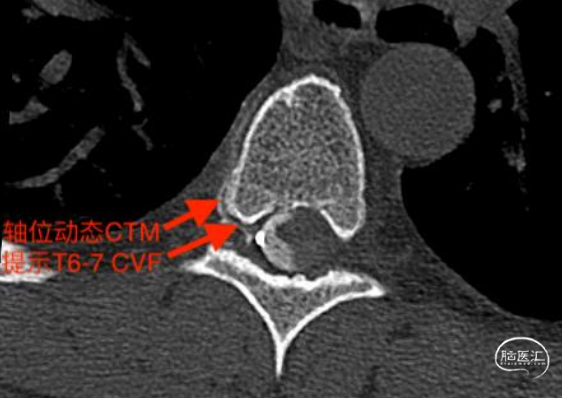

经CT脊髓造影发现瘘口,如上图。

3型瘘口,即脑脊液-静脉瘘(CVF)。此型瘘是没有真正的瘘口和漏液的,大多是发育异常导致蛛网膜下腔脑脊液和椎管静脉丛的直接沟通造成脑脊液从密闭的蛛网膜下腔系统流失,从而导致低脑脊液流量,产生症状。此型在椎管内是看不到漏液的,可能导致被错误的采用保守治疗,常延误病情。该型建议直接开椎手术处理。